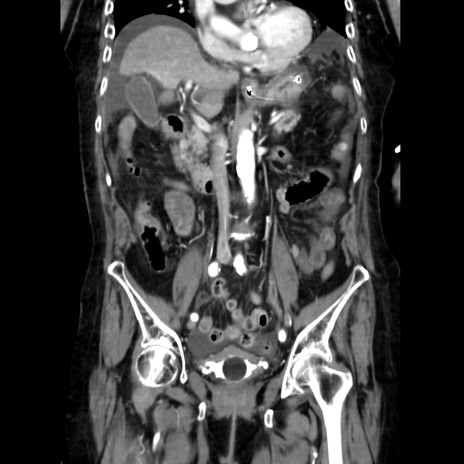

症例40(冠状断像)

【症例】90歳代女性

【主訴】腹痛・嘔吐

【現病歴】 食欲低下、嘔吐があり昨日他院受診。肺炎と診断され入院となる。入院後より腹部全体に圧痛あり。胃管留置され経過みていたが、症状持続するため、

当院転院となる。

【既往歴】胸椎圧迫骨折、胆石症

【身体所見】腹部:中央に激痛あり、圧痛あり、反跳痛不明

【データ】WBC 17100、CRP 18.82

冠状断像